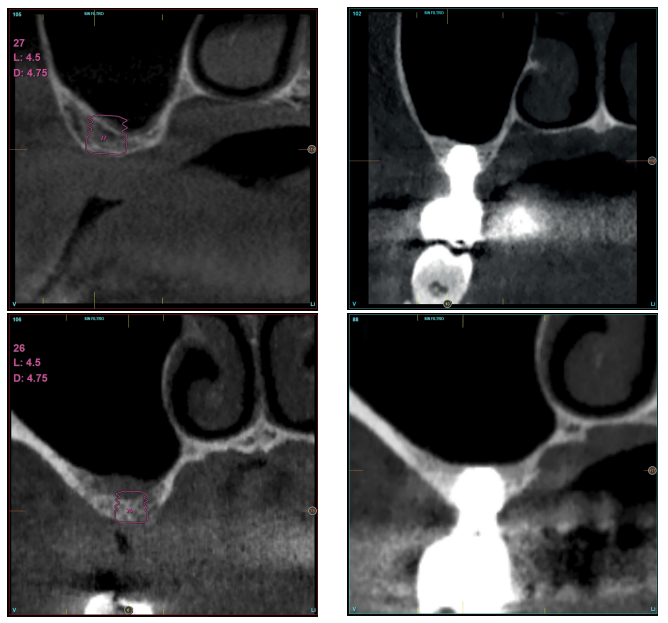

Fueron reclutados diez pacientes que cumplieron los criterios de inclusión, en los que fueron insertados 20 implantes. Tres de ellos fueron mujeres y la edad media fue de 72 (+/- 6 años). Ninguno de los pacientes era fumador en el momento de la cirugía y no presentaban enfermedad periodontal activa. El diámetro mayoritario de los implantes incluidos en el estudio fue de 5 mm (60%), seguido de 4,5, 5,5 y 4,75 mm (13,33% cada uno de ellos). La longitud predominante fue la de 5,5 mm (86,6% de los casos), siendo el 13,4% restante implantes de 4,5 mm de longitud. Las posiciones más habituales fueron para los segundos molares (molares 27 y 17) representando un 55% de los casos.

La altura media del volumen óseo residual fue de 3,1 mm (+/- 0,3 mm con un rango de 3-4 mm). En todos los casos se realizó una elevación de seno transcrestal, con hueso autólogo particulado obtenido del fresado de la zona de generación del neoalveolo para la inserción del implante, siendo la media de esta elevación sobre el ápice del implante en milímetros de 2,8 mm (+/- 0,99 rango 1,9 -5 mm). En el TAC de control al año de carga de los implantes estudiados, se mantiene la ganancia ósea lograda, no observándose disminución del volumen ganado, únicamente tres casos mostraron una disminución de entre 0,4 y 0,5 mm del volumen inicial al final (Tabla).

En las Figuras 2- 19 se muestra uno de los casos incluidos en el estudio.

previamente con el anclaje del implante en la porción vestibular de la cresta ósea.

la oseointegración del implante 6 meses después de la cirugía. Se observa una ganancia ósea de 4 mm.

en altura de 3,4 mm, siendo más uniforme en esta ocasión en toda la zona de la cresta. Se planifica un implante de 4,5 mm de longitud y

4,75 mm de diámetro.

implante y el volumen óseo ganado y conservado tras la función de los implantes.